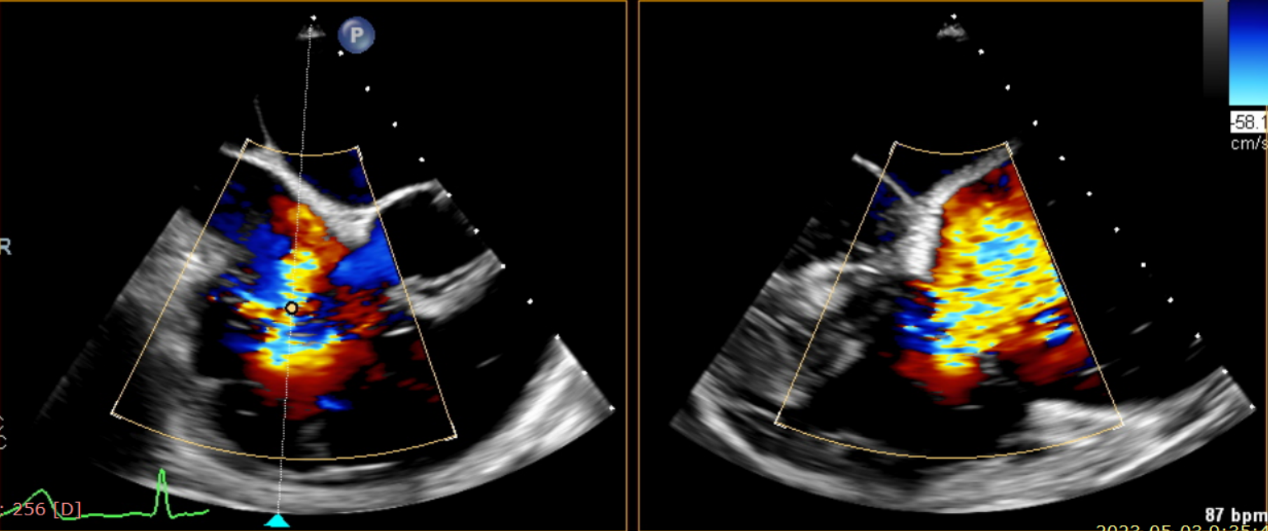

第二名患者是一位72歲的女性,既往有心力衰竭、冠狀動脈疾病、高血壓、高脂血癥、糖尿病、陣發(fā)性房顫的病史。她曾多次由于呼吸急促和下肢水腫到醫(yī)院就診。本次入院的原因是由于加重的心衰和三尖瓣關閉不全所導致的呼吸急促。

術前超聲提示大量三尖瓣反流

術中輸送器在超聲引導下調整位置

術后超聲提示僅殘余輕微瓣周漏